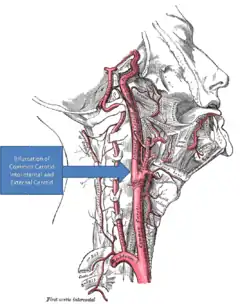

Reduced partial pressures of oxygen in the arteries due to intermittent hypoxia are sensed by and stimulate the carotid body, a chemoafferent receptor.[6][7] The activated carotid body triggers the release of serotonin that attach to serotonin receptors on the surface of motoneurons, such as the phrenic motoneuron in the case of respiratory recovery.[5] This signal transduction pathway then uses downstream molecules such as TrkB,[8] BDNF,[8] and PKA[9] to increase the synaptic output of the involved motor neuron which in turn increases the motor output of the involved muscles and, thus, decreases functional impairment. As the amount of intermittent hypoxia changes the amount of serotonin release and, as a result, the amount of LTF, this process exhibits metaplasticity.[10] Metaplasticity occurs when the LTF is itself plastic or variable.